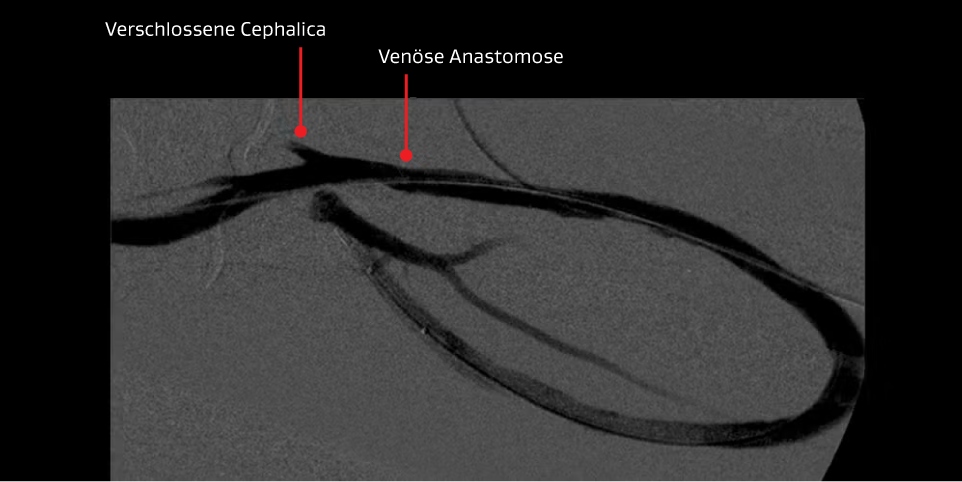

Zweite Intervention – Die PTA zur Thrombusentfernung war erneut die Behandlung der Wahl für die thrombosierte Prothese.

PTA-Verfahren zur Thrombusentfernung:

- Die erste Intervention war nur 12 Tage her.

- Der Patient stellte sich wieder mit einer thrombosierten Prothese vor, die gegenüber einer schweren venösen Anastomosenstenose zweitrangig war.

Ergebnis:

- Wieder wurde zunächst ein gutes Ergebnis der Angiografie mit wiederhergestelltem Blutfluss erzielt, jedoch kehrte der Patient 28 Tage später mit einer mit Gerinnseln verstopften Prothese zurück.

Abbildungen mit freundlicher Genehmigung von Minneapolis Vascular Physicians. Verwendet mit Genehmigung.